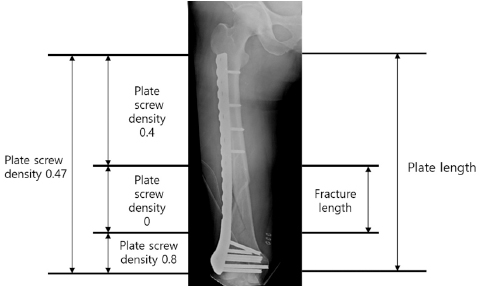

Fig. 8

(A) Schematic diagram showing the axial shape of the distal femur and the protrusion of distal locking screw. (B) True anteroposterior radiograph showing that the lengths of the distal locking screws appear to be appropriate. (C) Radiograph taken after rotating a thigh approximately 25° internally, showing the protrusion of multiple screws across the medial cortex.